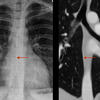

vessesls MR

Date: 02/25/2013

Views: 3222

normal vessels

Views: 3288